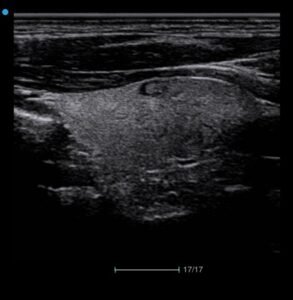

Elastografia

Wyposażony w zaawansowaną Elastografię Apogee 5500 przyczynia się do bezpiecznej i

dokładnej oceny chorób sutka.